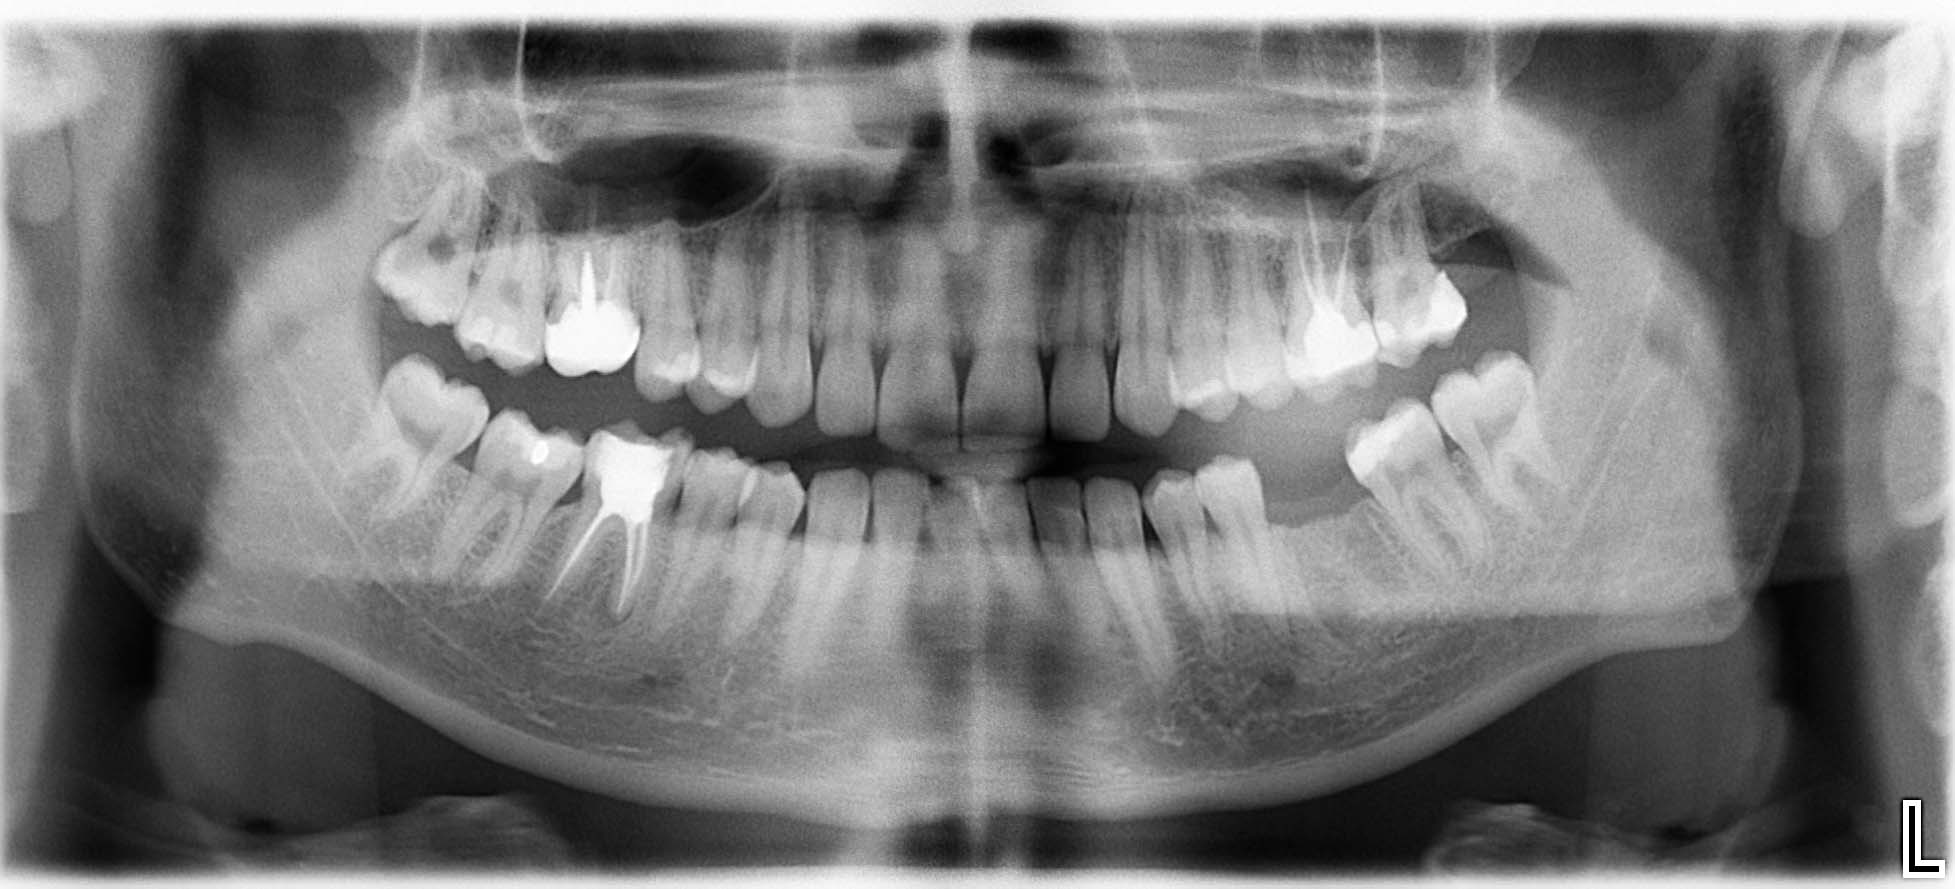

Ausgangssituation: Zahn 36 mit apikaler Beherdung, nicht erhaltungswürdig